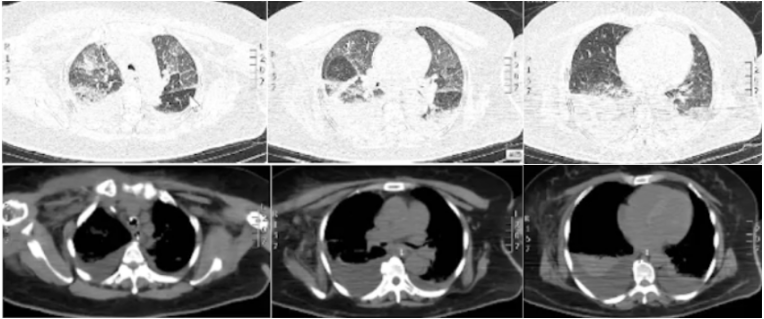

经抗感染治疗后患者仍反复发热,最高体温39.0°C。患者插管当天及插管后6天的血气分析和炎症指标如表1和表2所示,氧合较前好转,炎症指标下降。胸部X线片未见明显进展(图2)。

8月5日:拔管,序贯高流量氧疗,支气管镜下见隆突较多分泌物,气道黏膜无肿胀,远端气道未见分泌物。病原学结果陆续回报。【8月3日】肺泡灌洗液NGS回报鲍曼不动杆菌(序列数6152),人疱疹病毒1型(序列数215092),白色念珠菌(序列数3)。据此结果加用阿昔洛韦500 ivgtt q8h抗病毒。【8月7日】BALF培养鲍曼不动杆菌(++++),【8月8日】CVC导管尖端培养及痰培养结果均为鲍曼不动杆菌及白色念珠菌。8月8日:患者出现神志障碍,血氧饱和度低、呼吸浅快。血气分析(高流量湿化氧疗,氧浓度100%):pH 7.39,PaCO2 61 mmHg,PaO2 81 mmHg,HCO3- 36.9 mmol/L,SaO2 96%。考虑存在Ⅱ型呼吸衰竭及肺性脑病,遂再次经口气管插管,气管镜下见气道黏膜水肿明显,各支气管见大量白色黏稠痰液。血常规检查:WBC 6.72×109/L,Hb 77 g/L,NEU% 90.5%,PCT 1.30 ng/ml,CRP 126.0 mg/L。加用伏立康唑200 mg ivgtt q12h(首剂400 mg)抗真菌,硫酸黏菌素75万IU q12h持续微量泵入+25万IU q12h雾化吸入,以覆盖不动杆菌属。药敏试验结果提示泛耐药鲍曼不动杆菌,对黏菌素/多黏菌素、复方新诺明敏感,对替加环素中度敏感。插管第2天(8月9日)复查胸部CT:右上肺实变较前明显加重,双侧胸腔积液较前明显增多(图3)。更改抗生素治疗后患者仍每日发热,但最高体温较前稍下降,波动于38.0~38.5°C之间,8月10日两次血培养结果提示白色念珠菌(需氧瓶1天7小时及1天8小时报阳),8月12日停用万古霉素,改为利奈唑胺600 mg ivgtt q12h治疗。8月8日及8月12日炎症指标变化如表3所示。由于患者无法脱机拔管,为求进一步诊治,于8月13日转至我科ICU。患者自起病以来前期精神、睡眠一般,现插管镇静镇痛状态,大便正常,小便量明显减少,体重无法评估。体温37.2℃,脉搏90次/分,呼吸20次/分,血压140/86 mmHg,SpO2 95%(经口气管插管接有创机械通气,APV-CMV模式,氧浓度70%,潮气量320 ml,机控频率15次/分,PEEP 5 cmH2O)。患者肥胖体型,营养良好,神志清楚;双肺叩诊清音,双下肺可闻及部分湿啰音;心界无扩大,心率90次/分,律齐,无杂音;腹部平软,全腹无压痛及腹肌紧张,肝、脾肋缘下未触及,肠鸣音正常。双下肢轻度凹陷性水肿,双下肢皮肤无色素沉着。右侧腹股沟处可见皮肤破损,有脓性分泌物。肛门皮肤红肿,无明显溃烂。中年女性,急性病程;主要症状为下肢疼痛活动受限,局部有感染,持续发热,少尿;查血象、感染指标高,有血源及肺部感染;拔管后短时间内再插管,后续脱机拔管困难。①脓毒血症,血流感染,皮肤软组织感染,急性肾损害,低蛋白血症,中度贫血;②重症肺炎,Ⅱ型呼吸衰竭;③双侧股骨头缺血性坏死并右侧髋关节脱位;④右股骨上段骨折内固定术后;⑤2型糖尿病。患者入我科之前,颈内静脉导管尖端培养、痰培养、血及BALF培养均提示泛耐药鲍曼不动杆菌。对黏菌素/多黏菌素、复方新诺明、 米诺环素敏感,对替加环素中度敏感。